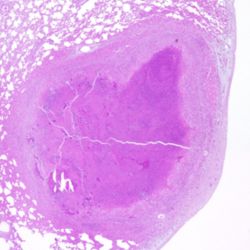

Pàgina anterior de 637 Pàgina següent 3181 total Canine Specie: Canine Organ: Eye Lesion: Edema Lesion modifier: - Disease: Infectious canine hepatitis Position: 291 (3 views) Caprine Specie: Caprine Organ: Lung Lesion: Pneumonia Lesion modifier: Pneumonia - Granulomatous Disease: Tuberculosis Files/Expedient: Sesc-TBC Position: 66 (9 views) Caprine Specie: Caprine Organ: Lung Lesion: Pneumonia Lesion modifier: Pneumonia - Granulomatous Disease: Tuberculosis Files/Expedient: Sesc-TBC Position: 90 (7 views) Caprine Specie: Caprine Organ: Lung Lesion: Pneumonia Lesion modifier: Pneumonia - Granulomatous Disease: Tuberculosis Files/Expedient: Sesc-TBC Position: 116 (6 views) Caprine Specie: Caprine Organ: Lung Lesion: Pneumonia Lesion modifier: Pneumonia - Granulomatous Disease: Tuberculosis Files/Expedient: Sesc-TBC Position: 25 (19 views) Pàgina anterior de 637 Pàgina següent Títol Select...Avian (Exotic) (110)Avian (Poultry) (76)Bovine (317)Canine (935)Caprine (47)Equine (257)Feline (326)Ferret (19)General (127)Marine mammal (22)Non-human primate (20)Ovine (328)Porcine (379)Rabbit (61)Reptile (38)Rodent (28)Wildlife (91) Format Select...- (60)Abomasum (37)Adrenal gland (10)Blood (7)Blood vessel (50)Body as a whole (19)Bone (57)Bone marrow (21)Brain (93)Cloaca (1)Diaphragm (2)Ear (5)Esophagus (39)Eye (16)Fetus (12)Gallbladder (23)Gizzard (2)Heart (265)Intestine (356)Joint (32)Kidney (443)Larynx (5)Liver (326)Lung (264)Lymph node (91)Mammary gland (10)Mediastinum (1)Muscle (22)Nasal cavity (22)Nerve (7)Omasum (5)Oral cavity (63)Ovary (14)Oviduct (8)Pancreas (7)Parathyroid (5)Penis (10)Peritoneum (65)Pharynx (9)Pituitary gland (6)Placenta (7)Prostate (8)Proventriculus (3)Reticulum (1)Rumen (28)Sinus (7)Skin (181)Spinal cord (15)Spleen (105)Stomach (125)Teeth (1)Testicle (11)Thoracic cavity (31)Thymus (13)Thyroid gland (5)Tongue (32)Tonsils (11)Trachea (11)Urethra (5)Urinay bladder (61)Uterus (27)Vagina (1)Vulva (1)Yolk sac (1) Cobertura Select...- (152)Abomasitis (26)Abscess (27)Acidosis (1)Adenocarcinoma (20)Adenoma (9)Aerosacculitis (6)Agenesis (1)Agnathia (1)Alopecia (7)Amyloidosis (12)Aneurysm (6)Angiectasis (1)Anthracosis (1)Arteritis (11)Arthritis (15)Arthrogryposis (6)Artifact (4)Ascites (13)Atelectasis (8)Atherosclerosis (5)Atresia (1)Atrial septal defect (2)Atrophy (10)Autolysis (7)Bronchitis (6)Bronchopneumonia (26)Cachexia (2)Carcinoma (103)Cardiomyopathy (19)Cellulitis (2)Chemodectoma (4)Cholangiohepatitis (4)Cholangitis (19)Cholecystitis (4)Cholestasis (5)Chondrodysplasia (2)Chondrosarcoma (2)Chronic passive congestion (13)Chylothorax (2)Cirrhosis (6)Coelomitis (3)Coenurus cerebralis (4)Colitis (40)Congestion (17)Conjunctivitis (5)Coronitis (3)Cryptorchidism (3)Cyst (25)Cystitis (24)Dermatitis (69)Diaphragmatic hernia (4)Dilation (28)Discospondylitis (1)Disseminated intravascular coagulation (7)Dyschondroplasia (1)Dysplasia (29)Ectopia cordis (1)Ectopic ureter (1)Edema (55)Emphysema (5)Encephalitis (5)Endocardiosis (14)Endocarditis (26)Endometritis (5)Enteritis (118)Enterolith (6)Epulis (3)Esophagitis (14)Fasciitis (1)Fibrosis (7)Fibrous osteodystrophy (8)Fistula (1)Folliculitis (3)Fracture (2)Gastritis (34)Gingivitis (5)Glioma (8)Glomerulonephritis (21)Glossitis (25)Glycogenosis (1)Gout (8)Granuloma (2)Granulosa cell tumor (4)Hemangioma (9)Hemangiosarcoma (46)Hematoma (8)Hemoglobinuria (2)Hemopericardium (12)Hemoperitoneum (2)Hemorrhage (100)Hemosiderosis (7)Hemothorax (2)Hepatitis (78)Hernia (11)Histiocytosis (3)Hydatid cyst (11)Hydrocephalus (9)Hydrometra (1)Hydronephrosis (22)Hydropericardium (6)Hydrothorax (3)Hydroureter (5)Hyperkeratosis (8)Hyperostosis (4)Hyperplasia (37)Hypertrophy (9)Hypopigmentation (1)Hypoplasia (7)Hypopyon (1)Impaction (6)Infarction (63)Insulinoma (6)Intussusception (5)Jaundice (17)Laminitis (2)Laryngitis (2)Leiomyoma (5)Leukemia (13)Lipidosis (36)Lipoma (7)Lymphadenitis (45)Lymphadenopathy (7)Lymphangiectasia (6)Lymphangitis (5)Lymphoma (221)Malacia (11)Malignant melanoma (15)Mast cell tumor (11)Mastitis (8)Megaesophagus (2)Melanosis (3)Melena (4)Meningioma (6)Meningitis (6)Meningocele (2)Meningoencephalitis (5)Mesothelioma (5)Methemoglobinemia (2)Mineralization (10)Mucocele (5)Mucometra (1)Multilobular bone tumor (1)Mummification (3)Myelofibrosis (1)Myocarditis (4)Myositis (5)Necrosis (81)Nephritis (113)Nephroblastoma (6)Nephrosclerosis (1)Nephrosis (14)Neuritis (1)Obstruction (13)Omasitis (4)Omphalitis (1)Omphalophlebitis (7)Orchitis (4)Osteoarthrosis (5)Osteomyelitis (9)Otitis (2)Palatoschisis (3)Pancreatitis (3)Panniculitis (3)Papilloma (7)Parakeratosis (14)Patent ductus arteriosus (6)Peliosis hepatis (1)Perforation (17)Pericarditis (35)Peritonitis (39)Persistent right aortic arch (1)Pharyngitis (2)Pheochromocytoma (2)Phlebitis (2)Placentitis (6)Pleuritis (21)Pleuropneumonia (24)Pneumonia (109)Pneumothorax (3)Polycystosis (14)Polyp (5)Polyserositis (6)Posthitis (1)Proctitis (4)Prolapse (3)Prostatitis (3)Proventriculitis (1)Pyelonephritis (24)Pyometra (6)Pyothorax (4)Rhinitis (11)Rumenitis (6)Rupture (24)Salpingitis (3)Sarcoma (57)Sclerosis (1)Scoliosis (2)Seminoma (2)Sequestrum (2)Serous atrophy (14)Sinusitis (7)Splenitis (14)Splenomegaly (9)Spondylitis (6)Spondylosis (1)Stenosis (9)Stomatitis (32)Tenosynovitis (2)Teratoma (3)Thricobezoar (2)Thrombosis (16)Tonsilitis (4)Torsion (13)Tracheitis (4)Tympany (7)Typhlitis (8)Typhlocolitis (4)Ulcer (43)Urethritis (1)Urolithiasis (36)Uroperitoneum (1)Uveitis (1)Vasculitis (15)Ventricular septal defect (3)Volvulus (11) Matèria Select... - (14)- (1653)- (152)Abomasitis - Catarrhal (2)Abomasitis - Catarrhal-hemorrhagic (1)Abomasitis - Chronic (1)Abomasitis - Fibrinous-necrotizing (2)Abomasitis - Hyperplasic (5)Abomasitis - Hyperplasic - Chronic (1)Abomasitis - Necrotic (1)Abomasitis - Necrotizing (2)Abomasitis - Ulcerative (5)Adenocarcinoma (9)Aerosacculitis - Granulomatous (1)Amyloidosis - Chronic (1)Arteritis - Necrotic (2)Arteritis - Necrotizing (1)Arthritis - Chronic (4)Arthritis - Fibrinous-purulent (3)Arthritis - Serous (4)Arthritis - Subacute (1)Ascites - Serous (1)Atrophy - Serous (1)Bronchitis - Catarrhal (3)Bronchitis - Suppurative (1)Bronchopneumonia - Catarrhal-purulent (17)Bronchopneumonia - Fibrinous (1)Bronchopneumonia - Granulomatous (1)Bronchopneumonia - Purulent (1)Bronchopneumonia - Suppurative (5)Carcinoma - Adenocarcinoma (33)Carcinoma - Adenocarcinoma - Hepatocellular (2)Carcinoma - Adenocarcinoma - Mucinous (1)Carcinoma - Basosquamous (1)Carcinoma - Cholangiocellular (3)Carcinoma - Hepatocellular (4)Carcinoma - Metastatic (3)Carcinoma - Squamous cell carcinoma (13)Carcinoma - Transitional cell (2)Cardiomyopathy - Dilated (13)Cardiomyopathy - Hypertrophic (6)Cellulitis - Necrotizing (1)Cholangitis - Chronic (8)Cholangitis - Hyperplasic (3)Cholecystitis - Fibrinous-necrotizing (1)Coelomitis - Fibrinous (1)Coelomitis - Granulomatous (1)Colitis - Catarrhal (3)Colitis - Catarrhal-hemorrhagic (1)Colitis - Fibrinous (1)Colitis - Fibrinous-necrotizing (1)Colitis - Fibrinous-necrotizing (Diphtheritic) (6)Colitis - Granulomatous (2)Colitis - Hemorrhagic (4)Colitis - Hemorrhagic-necrotizing (3)Colitis - Necrotizing (2)Colitis - Ulcerative (6)Congestion - Chronic (2)Conjunctivitis - Hyperplasic (1)Conjunctivitis - Purulent (3)Coronitis - Ulcerative (1)Cystitis - Chronic (3)Cystitis - Fibrinous (1)Cystitis - Fibrinous-necrotizing (1)Cystitis - Follicular (1)Cystitis - Hemorrhagic (6)Cystitis - Hemorrhagic-ulcerative (1)Cystitis - Necrotizing (9)Cystitis - Perforated (1)Dermatitis - Granulomatous (14)Dermatitis - Hyperkeratotic (10)Dermatitis - Hyperplasic (proliferative) (1)Dermatitis - Hyperplastic (10)Dermatitis - Necrotizing (4)Dermatitis - Pustular (4)Dermatitis - Ulcerative (2)Dilation - Chronic (1)Discospondylitis - Necrotizing (1)Dysplasia - Follicular (5)Edema - Interstitial (6)Emphysema - Interstitial (1)Encephalitis - Granulomatous (1)Encephalitis - Nonsuppurative (1)Endocardiosis - Mitral (7)Endocardiosis - Mitral - Chronic (5)Endocarditis - Valvular (6)Endocarditis - Valvular - Mitral (7)Endocarditis - Valvular - Pulmonic (1)Endocarditis - Valvular - Subacute (1)Endocarditis - Valvular - Subaortic (5)Endocarditis - Valvular - Tricuspid (4)Endometritis - Purulent (3)Endometritis - Purulent-hemorrhagic (2)Enteritis - Catarrhal (23)Enteritis - Catarrhal - Acute (1)Enteritis - Catarrhal-hemorrhagic (5)Enteritis - Catarrhal-hemorrhagic - Acute (2)Enteritis - Fibrinous (16)Enteritis - Fibrinous - Acute (3)Enteritis - Fibrinous-necrotizing (7)Enteritis - Granulomatous (14)Enteritis - Granulomatous - Chronic (1)Enteritis - Granulomatous - Multifocal (1)Enteritis - Hemorrhagic (17)Enteritis - Hemorrhagic - Acute (1)Enteritis - Hemorrhagic-necrotizing (1)Enteritis - Hyperplasic (proliferative) (4)Enteritis - Necrotizing (4)Enteritis - Necrotizing - Acute (1)Enteritis - Necrotizing - Hemorrhagic (1)Enteritis - Necrotizing-ulcerative (2)Enteritis - Ulcerative (1)Enteritis - Ulcerative-hemorrhagic (1)Esophagitis - Erosive-ulcerative (6)Esophagitis - Necrotizing (4)Esophagitis - Ulcerative (1)Esophagitis - Ulcerative-necrotizing (1)Fasciitis - Fibrinous-purulent (1)Folliculitis - Purulent (2)Gastritis - Catarrhal (2)Gastritis - Chronic (1)Gastritis - Follicular (1)Gastritis - Hemorrhagic (2)Gastritis - Hemorrhagic-necrotizing (1)Gastritis - Hypertrophic (2)Gastritis - Inclusion bodies (1)Gastritis - Mineralization (1)Gastritis - Mycotic (1)Gastritis - Necrotizing (2)Gastritis - Ulcerative (6)Gastritis - Uremic (3)Gingivitis - Erosive (2)Gingivitis - Hyperplasic (proliferative) (1)Gingivitis - Necrotizing (1)Glomerulonephritis - Chronic (7)Glomerulonephritis - Membranoproliferative (3)Glomerulonephritis - Membranoproliferative - Chronic (1)Glomerulonephritis - Membranous (3)Glomerulonephritis - Membranous - Chronic (1)Glomerulonephritis - Proliferative (2)Glomerulonephritis - Subacute (1)Glossitis - Erosive (2)Glossitis - Granulomatous (6)Glossitis - Hyperplasic (1)Glossitis - Hyperplasic (proliferative) (2)Glossitis - Hyperplastic (1)Glossitis - Necrotizing (2)Glossitis - Necrotizing - Focal (1)Glossitis - Ulcerative (6)Glossitis - Ulcerative - Multifocal (1)Glossitis - Ulcerative - Subacute (1)Glycogenosis (1)Granuloma - Eosinophilic (1)Hemangiosarcoma - Metastatic (2)Hemorrhage - Acute (1)Hemorrhage - Subcapsular (3)Hepatitis - Abscess (9)Hepatitis - Acute (3)Hepatitis - Chronic (4)Hepatitis - Chronic interstitial (6)Hepatitis - Granulomatous (7)Hepatitis - Interstitial - Multifocal (1)Hepatitis - Interstitial - Subacute (1)Hepatitis - Necrotizing (17)Hepatitis - Necrotizing - Acute (2)Hepatitis - Necrotizing - Hemorrhagic (1)Hepatitis - Necrotizing - Subacute (1)Hepatitis - Pyogranulomatous (7)Hepatitis - Subacute (4)Hydronephrosis - Chronic (1)Hydropericardium - Chronic (1)Hyperplasia - Erythroid (1)Hyperplasia - Lymphoid (3)Hyperplasia - Myeloid (1)Hyperplasia - Nodular (8)Hypertrophy - Concentric (2)Hypertrophy - Eccentric (3)Infarction - Acute (17)Infarction - Acute - Multifocal (2)Infarction - Chronic (5)Infarction - Chronic - Multifocal (1)Infarction - Subacute (18)Infarction - Subacute - Focal (2)Laminitis - Chronic (2)Laryngitis - Necrotic (1)Laryngitis - Necrotizing (1)Leukemia - Lymphoid leukemia (2)Leukemia - Non-lymphoid leukemia (6)Lipidosis - Multifocal (1)Lipidosis - Panlobular (1)Lipidosis - Panlobular - Generalized (2)Lymphadenitis - Granulomatous (24)Lymphadenitis - Granulomatous - Chronic (3)Lymphadenitis - Hemorrhagic (1)Lymphadenitis - Necrotizing (5)Lymphadenitis - Necrotizing (caseous) (11)Lymphangitis - Granulomatous (1)Lymphangitis - Purulent (1)Lymphangitis - Ulcerative (1)Lymphoma - Alimentary lymphoma (7)Lymphoma - Cutaneous lymphoma (6)Lymphoma - Lymphosarcoma (2)Lymphoma - Mediastinal lymphoma (1)Lymphoma - Multicentric lymphoma (29)Malignant melanoma - Malignant (1)Malignant melanoma - Metastatic (1)Mast cell tumor - Metastatic (1)Mastitis - Fibrinous-purulent (2)Mastitis - Necrotic (1)Mastitis - Purulent (3)Mastitis - Suppurative (1)Meningitis - Fibrinous-purulent (2)Meningitis - Purulent (4)Meningoencephalitis - Necrotizing (3)Meningoencephalitis - Nonsuppurative (2)Mineralization - Metastatic (4)Myocarditis - Fibrous - Chronic (1)Myocarditis - Granulomatous (1)Myositis - Purulent (2)Necrosis - Acute (1)Necrosis - Cortical (5)Necrosis - Follicular (1)Necrosis - Papillary (8)Necrosis - Papillary - Acute (3)Necrosis - Subacute (3)Necrosis - Tubular (6)Nephritis - Embolic (2)Nephritis - Embolic suppurative (7)Nephritis - Granulomatous (27)Nephritis - Granulomatous - Chronic (1)Nephritis - Granulomatous - Multifocal (1)Nephritis - Interstitial (6)Nephritis - Interstitial - Acute (4)Nephritis - Interstitial - Chronic (41)Nephritis - Interstitial - Subacute (12)Nephritis - Purulent (7)Nephritis - Purulent - Acute (2)Nephritis - Purulent - Multifocal (3)Nephrosis - Cholemic (3)Nephrosis - Hemoglobinuric (10)Omasitis - Fibrinous-necrotizing (1)Omasitis - Hyperkeratotic (1)Omasitis - Necrotizing (2)Omphalophlebitis - Fibrinous-purulent (2)Omphalophlebitis - Purulent (3)Orchitis - Necrotizing (1)Osteomyelitis - Necrotizing (7)Osteomyelitis - Purulent (2)Otitis - Necrotizing (1)Otitis - Proliferative (1)Pancreatitis - Acute (1)Pancreatitis - Chronic (1)Pancreatitis - Granulomatous (1)Panniculitis - Fibrinous-purulent (1)Panniculitis - Necrotic (1)Panniculitis - Parasitic (1)Perforation - Acute (2)Pericarditis - Fibrinous (19)Pericarditis - Fibrinous - Subacute (1)Pericarditis - Fibrinous-necrotizing (1)Pericarditis - Fibrinous-purulent (3)Pericarditis - Fibrous (1)Pericarditis - Fibrous - Chronic (1)Pericarditis - Gangrenous (6)Pericarditis - Granulomatous (1)Pericarditis - Granulomatous - Chronic (2)Peritonitis - Acute (1)Peritonitis - Fibrinous (11)Peritonitis - Fibrinous - Subacute (1)Peritonitis - Fibrinous-purulent (5)Peritonitis - Fibrous (3)Peritonitis - Granulomatous (6)Peritonitis - Purulent (1)Peritonitis - Purulent-hemorrhagic (1)Peritonitis - Pyogranulomatous (3)Pharyngitis - Fibrinous-necrotizing (1)Pharyngitis - Ulcerative (1)Pheochromocytoma - Metastatic (1)Phlebitis - Purulent (1)Placentitis - Fibrinous-necrotizing (1)Placentitis - Necrotic (1)Placentitis - Necrotizing (1)Pleuritis - Chronic (1)Pleuritis - Fibrinous (3)Pleuritis - Fibrinous-purulent (2)Pleuritis - Fibrous (2)Pleuritis - Granulomatous (3)Pleuritis - Hyperplastic (2)Pleuritis - Purulent (2)Pleuritis - Pyogranulomatous (1)Pleuropneumonia - Fibrinous (13)Pleuropneumonia - Fibrinous-necrotizing (5)Pleuropneumonia - Granulomatous (2)Pleuropneumonia - Hemorrhagic-necrotizing (4)Pneumonia - Aspiration (11)Pneumonia - Bronchointerstitial (4)Pneumonia - Bronchointerstitial - Subacute (1)Pneumonia - Embolic (5)Pneumonia - Granulomatous (37)Pneumonia - Granulomatous - Multifocal (4)Pneumonia - Hemorrhagic-necrotizing (2)Pneumonia - Interstitial (7)Pneumonia - Interstitial - Acute (8)Pneumonia - Interstitial - Chronic (6)Pneumonia - Interstitial - Subacute (15)Pneumonia - Necrotizing (2)Pneumonia - Pyogranulomatous (2)Pneumonia - Verminous (5)Polyserositis - Fibrinous (6)Polyserositis - Fibrous (1)Proctitis - Fibrinous-necrotizing (1)Proctitis - Parasitic (2)Prostatitis - Purulent (1)Pyelonephritis - Acute (2)Pyelonephritis - Chronic (3)Rhinitis - Catarrhal (2)Rhinitis - Fibrinous (1)Rhinitis - Granulomatous (4)Rhinitis - Purulent (3)Rumenitis - Acute (1)Rumenitis - Erosive (1)Rumenitis - Necrotizing (1)Rupture - Acute (3)Sarcoma - Fibrosarcoma (12)Sarcoma - Hemangiosarcoma (11)Sarcoma - Histiocytic (7)Sarcoma - Metastatic (1)Sarcoma - Multilobular tumor of bone (1)Sequestrum - Chronic (2)Sinusitis - Suppurative (1)Splenitis - Granulomatous (8)Splenitis - Granulomatous - Chronic (1)Splenitis - Necrotizing (3)Splenitis - Necrotizing (caseous) (2)Spondylitis - Necrotizing (2)Stenosis - Intestinal (1)Stenosis - Valvular - Subaortic (4)Stomatitis - Erosive (12)Stomatitis - Erosive-ulcerative (3)Stomatitis - Fibrinous-necrotizing (1)Stomatitis - Fibrinous-necrotizing (Diphtheritic) (1)Stomatitis - Granulomatous (1)Stomatitis - Hyperplasic (1)Stomatitis - Hyperplasic (proliferative) (1)Stomatitis - Necrotizing (2)Stomatitis - Ulcerative (5)Stomatitis - Ulcerative - Multifocal (1)Stomatitis - Ulcerative-necrotizing (1)Tonsilitis - Necrotizing (4)Torsion - Acute passive hyperemia (5)Tracheitis - Catarrhal (3)Tracheitis - Fibrinous (1)Tracheitis - Granulomatous (1)Typhlitis - Catarrhal (1)Typhlitis - Fibrinous-necrotizing (2)Typhlitis - Hemorrhagic (2)Typhlitis - Ulcerative-hemorrhagic (1)Typhlocolitis - Fibrinous-necrotizing (2)Typhlocolitis - Proliferative (1)Ulcer - Chronic (6)Ulcer - Multifocal (2)Ulcer - Mycotic (1)Ulcer - Perforated (6)Urethritis - Hemorrhagic (1)Urolithiasis - Chronic (2)Uveitis - Granulomatous (1)Vasculitis - Granulomatous (1)Vasculitis - Necrotizing (1) Editor Select...- (1970)Acidosis (2)Actinobacillosis (Pleuropneumonia) (11)Aelurostrongylosis (2)African horse sickness (13)African swine fever (14)Alopecia X (1)Anaplasmosis (4)Anthrax (2)Aortic thromboembolism (feline) (7)Ascariasis (15)Aspergillosis (18)Atopic dermatitis (1)Atrophic rhinitis (3)Babesiosis (6)Blackhead (1)Bluetongue (11)Border disease (2)Bovine viral diarrhea (21)Brucellosis (2)Candidiasis (5)Canine distemper (14)Caprine arthritis-encephalitis (2)Capture myopathy (1)Cardiac insufficiency (17)Caseous lymphadenitis (7)Chlamydiosis (2)Classical swine fever (19)Clostridiosis (19)Coccidiosis (9)Coenurosis (4)Colibacillosis (21)Contagious ecthyma (7)Copper toxicosis (11)Cowdriosis (Heartwater) (3)Cryptococcosis (3)Cryptosporidiosis (2)Cysticercosis (23)Demodicosis (1)Diabetes (1)Dicrocoeliosis (5)Dictyocaulosis (4)Dirofilariasis (7)Discoid lupus erythematosus (3)Echinococcosis (17)Edema disease (7)Egg drop syndrome (1)Encephalitozoonosis (5)Enterotoxemia (1)Enzootic bovine leukosis (46)Epitheliogenesis imperfecta (3)Equine rhinopneumonitis (2)Equine verminous arteritis (strongylosis) (7)Erysipelas (5)Exudative epidermitis (7)Fasciolasis (11)Feline eosinophilic dermatoses (1)Feline hepatic lipidosis (8)Feline histiocytosis (4)Feline infectious peritonitis (38)Feline leukemia (4)Feline lower urinary tract disease (3)Feline panleukopenia (16)Feline viral rhinotracheitis (1)Flea allergy dermatitis (1)Foot and mouth disease (2)Gasterophilosis (4)Glasser's disease (15)Gousiekte (4)Gout (6)Haemonchosis (9)Hemolytic anemia (4)Hemorrhagic diathesis (1)Hepatic insufficiency (11)Hepatosis dietetica (7)Herpesvirosis (6)Hyperadrenocorticism (7)Hyperparathyroidism (10)Hypertrophic osteopathy (6)Hypervitaminosis D (1)Hypodermosis (1)Inclusion body hepatitis (4)Infectious bovine rhinotracheitis (5)Infectious bronchitis (5)Infectious canine hepatitis (13)Influenza (4)Juvenile nephropathy (8)Lamb dysentery (4)Leishmaniasis (28)Leptospirosis (1)Leukosis (5)Listeriosis (4)Lumpy skin disease (3)Maedi-visna (4)Malignant catarrhal fever (12)Mange (6)Mannheimiosis (5)Marek's disease (7)Metabolic bone disease (2)Mucoid enteropathy (5)Mulberry heart disease (5)Myasis (1)Mycobacteriosis (22)Mycosis fungoides (6)Myxomatosis (3)Necrobacillosis (5)Neonatal isoerythrolysis (6)Nocardiosis (4)Oestrosis (2)Onchocerciasis (1)Osteochondrosis (1)Ostertagiosis (6)Ovine pulmonary adenocarcinoma (5)Oxyuriasis (1)Pacheco's disease (4)Papillomatosis (6)Paratuberculosis (18)Parvovirosis (17)Pasteurellosis (11)Pemphigus foliaceus (1)Periodontal disease (1)Polioencephalomalacia of ruminants (4)Polyarteritis nodosa (3)Polycystic kidney disease (13)Porcine circovirosis (11)Porcine dermatitis and nephropathy syndrome (9)Porcine proliferative enteropathy (4)Porcine reproductive and respiratory syndrome (6)Porcine stress syndrome (1)Pox (13)Pregnancy toxemia (3)Proventricular dilatation disease (2)Pseudotuberculosis (yersiniosis) (2)Psittacine beak and feather disease (PBFD) (5)Pyoderma (4)Q fever (4)Rabbit hemorrhagic disease (2)Renal insufficiency (12)Reticuloendotheliosis (2)Rhodococcosis (1)Rickets (1)Rinderpest (2)Salmonellosis (34)Sarcosporidiosis (2)Schmallenberg (7)Septicemia (23)Spirocercosis (11)Streptococcosis (5)Strongylosis (1)Swine dysentery (5)Systemic coronavirosis (5)Tetralogy of Fallot (5)Theileriosis (13)Thromboembolism (5)Toxoplasmosis (11)Transmissible viral proventriculitis (1)Traumatic reticuloperitonitis (3)Traumatism (16)Tuberculosis (58)Ulcerative lymphangitis (1)Uremic syndrome (20)Viral arthritis (6)White muscle disease (9)Wobbler syndrome (2)Xanthomatosis (1)Zygomycosis (4) Idioma Select...- (1180)Bacterial (501)Degeneration (106)Fungal (46)Hemodynamic (112)Idiopathic (22)Inflammation (58)Malformation (88)Neoplasia (343)Nutritional (41)Parasitic (243)Physical/Chemical (93)Toxic (44)Viral (304) Ítem destacat Porcine Sow. Porcine Ulcerative Dermatitis Syndrome (PUDS). Interface dermatitis. Lesions were neither painful nor pruritic. University of Pretoria, South…